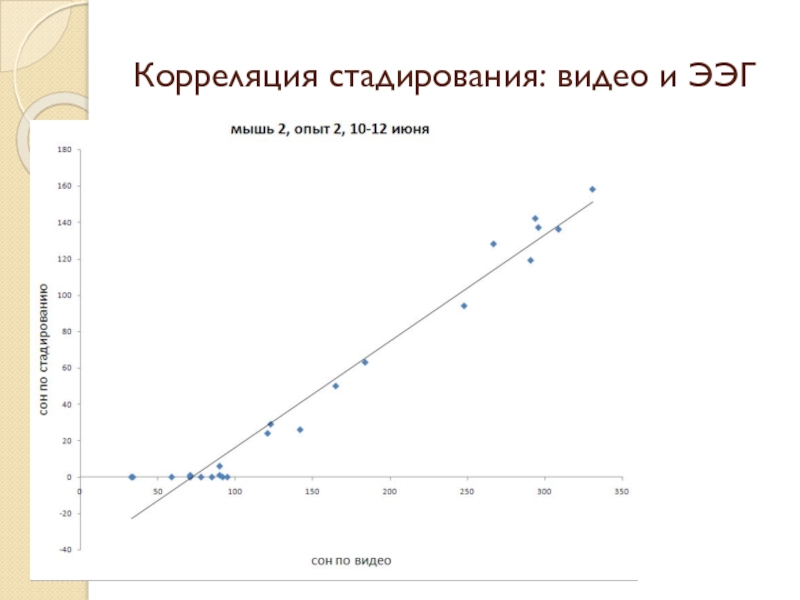

- 24. Корреляция стадирования: видео и ЭЭГ